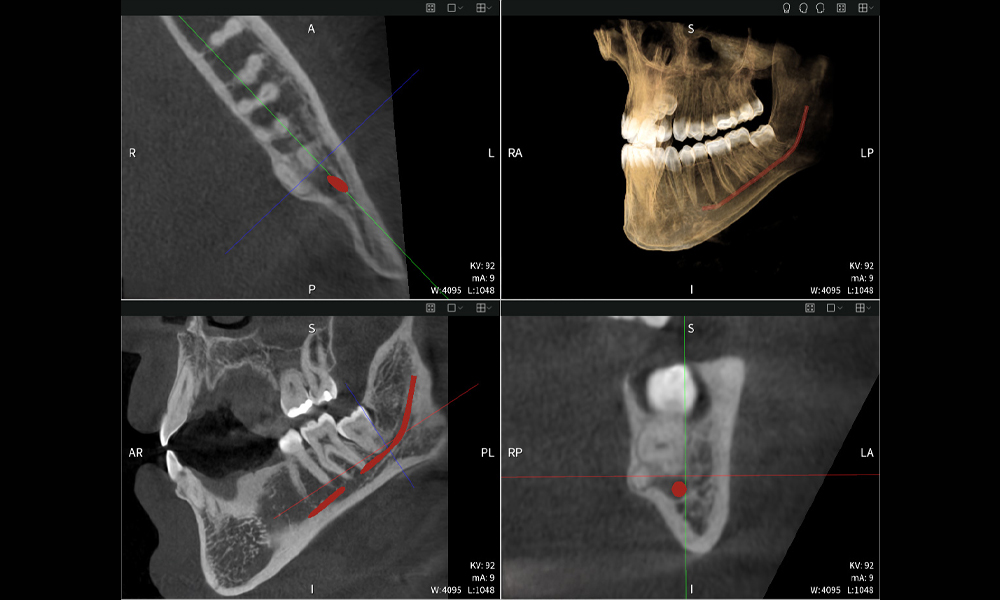

Below you will find a case from Dr. med. dent. Oliver A. Centrella, in which the CBCT images obtained with Seethrough Max provided crucial information on the complex anatomy and the critical relationship between the wisdom teeth and the inferior alveolar nerve. In this case, there is a indication for the surgical removal of the wisdom teeth.

Figure a: Imaging results of Seethrough Max, in front of a black background.

• Top left: Axial cross-section of the left mandible (region 38) showing the inferior alveolar nerve (red) in proximity to the roots of tooth 38.

• Top right: 3D reconstruction of the entire mandible for orientation. The red-marked inferior alveolar nerve illustrates its location within the jawbone.

• Bottom left: Sagittal view of the mandible (region 38), highlighting the close spatial relationship between the roots and the nerve canal.

• Bottom right: Coronal view of the mandible (region 38), which is crucial for assessing the spatial position of the roots relative to the nerve.